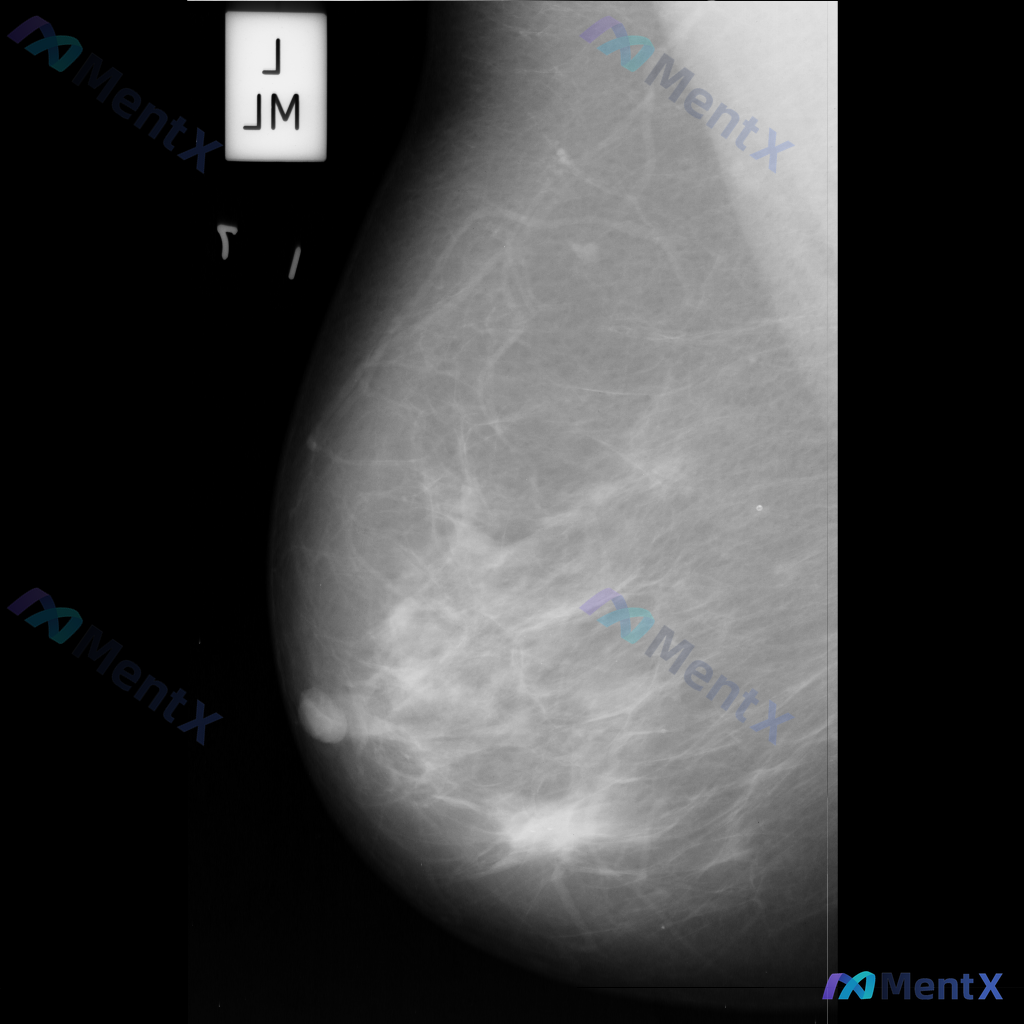

整理到一份乳腺影像的分析资料,想请大家一起讨论看看。 基本信息: - 影像类型:左侧乳腺钼靶内外斜位(MLO) 影像主要表现: 1. 左侧乳腺中上部及外侧可见局灶性结构扭曲 2. 乳腺腺体组织以纤维腺体为主,密度较高,为不均匀致密型(ACR BI-RADS C型) 3. 腺体可见多发斑片状、结节状高...

各位同道好,今天分享一则左乳钼靶病例,影像表现如下: 1. 左乳下方(近乳头区)可见一个边界清晰、形态卵圆形的等/稍高密度肿块影; 2. 左乳中央及下象限腺体局部密度增高和结构紊乱; 3. 散在分布的粗大点状钙化。 上传的钼靶影像编号为mdb083.png,供大家参考。 针对这组表现,你更倾向于哪种...